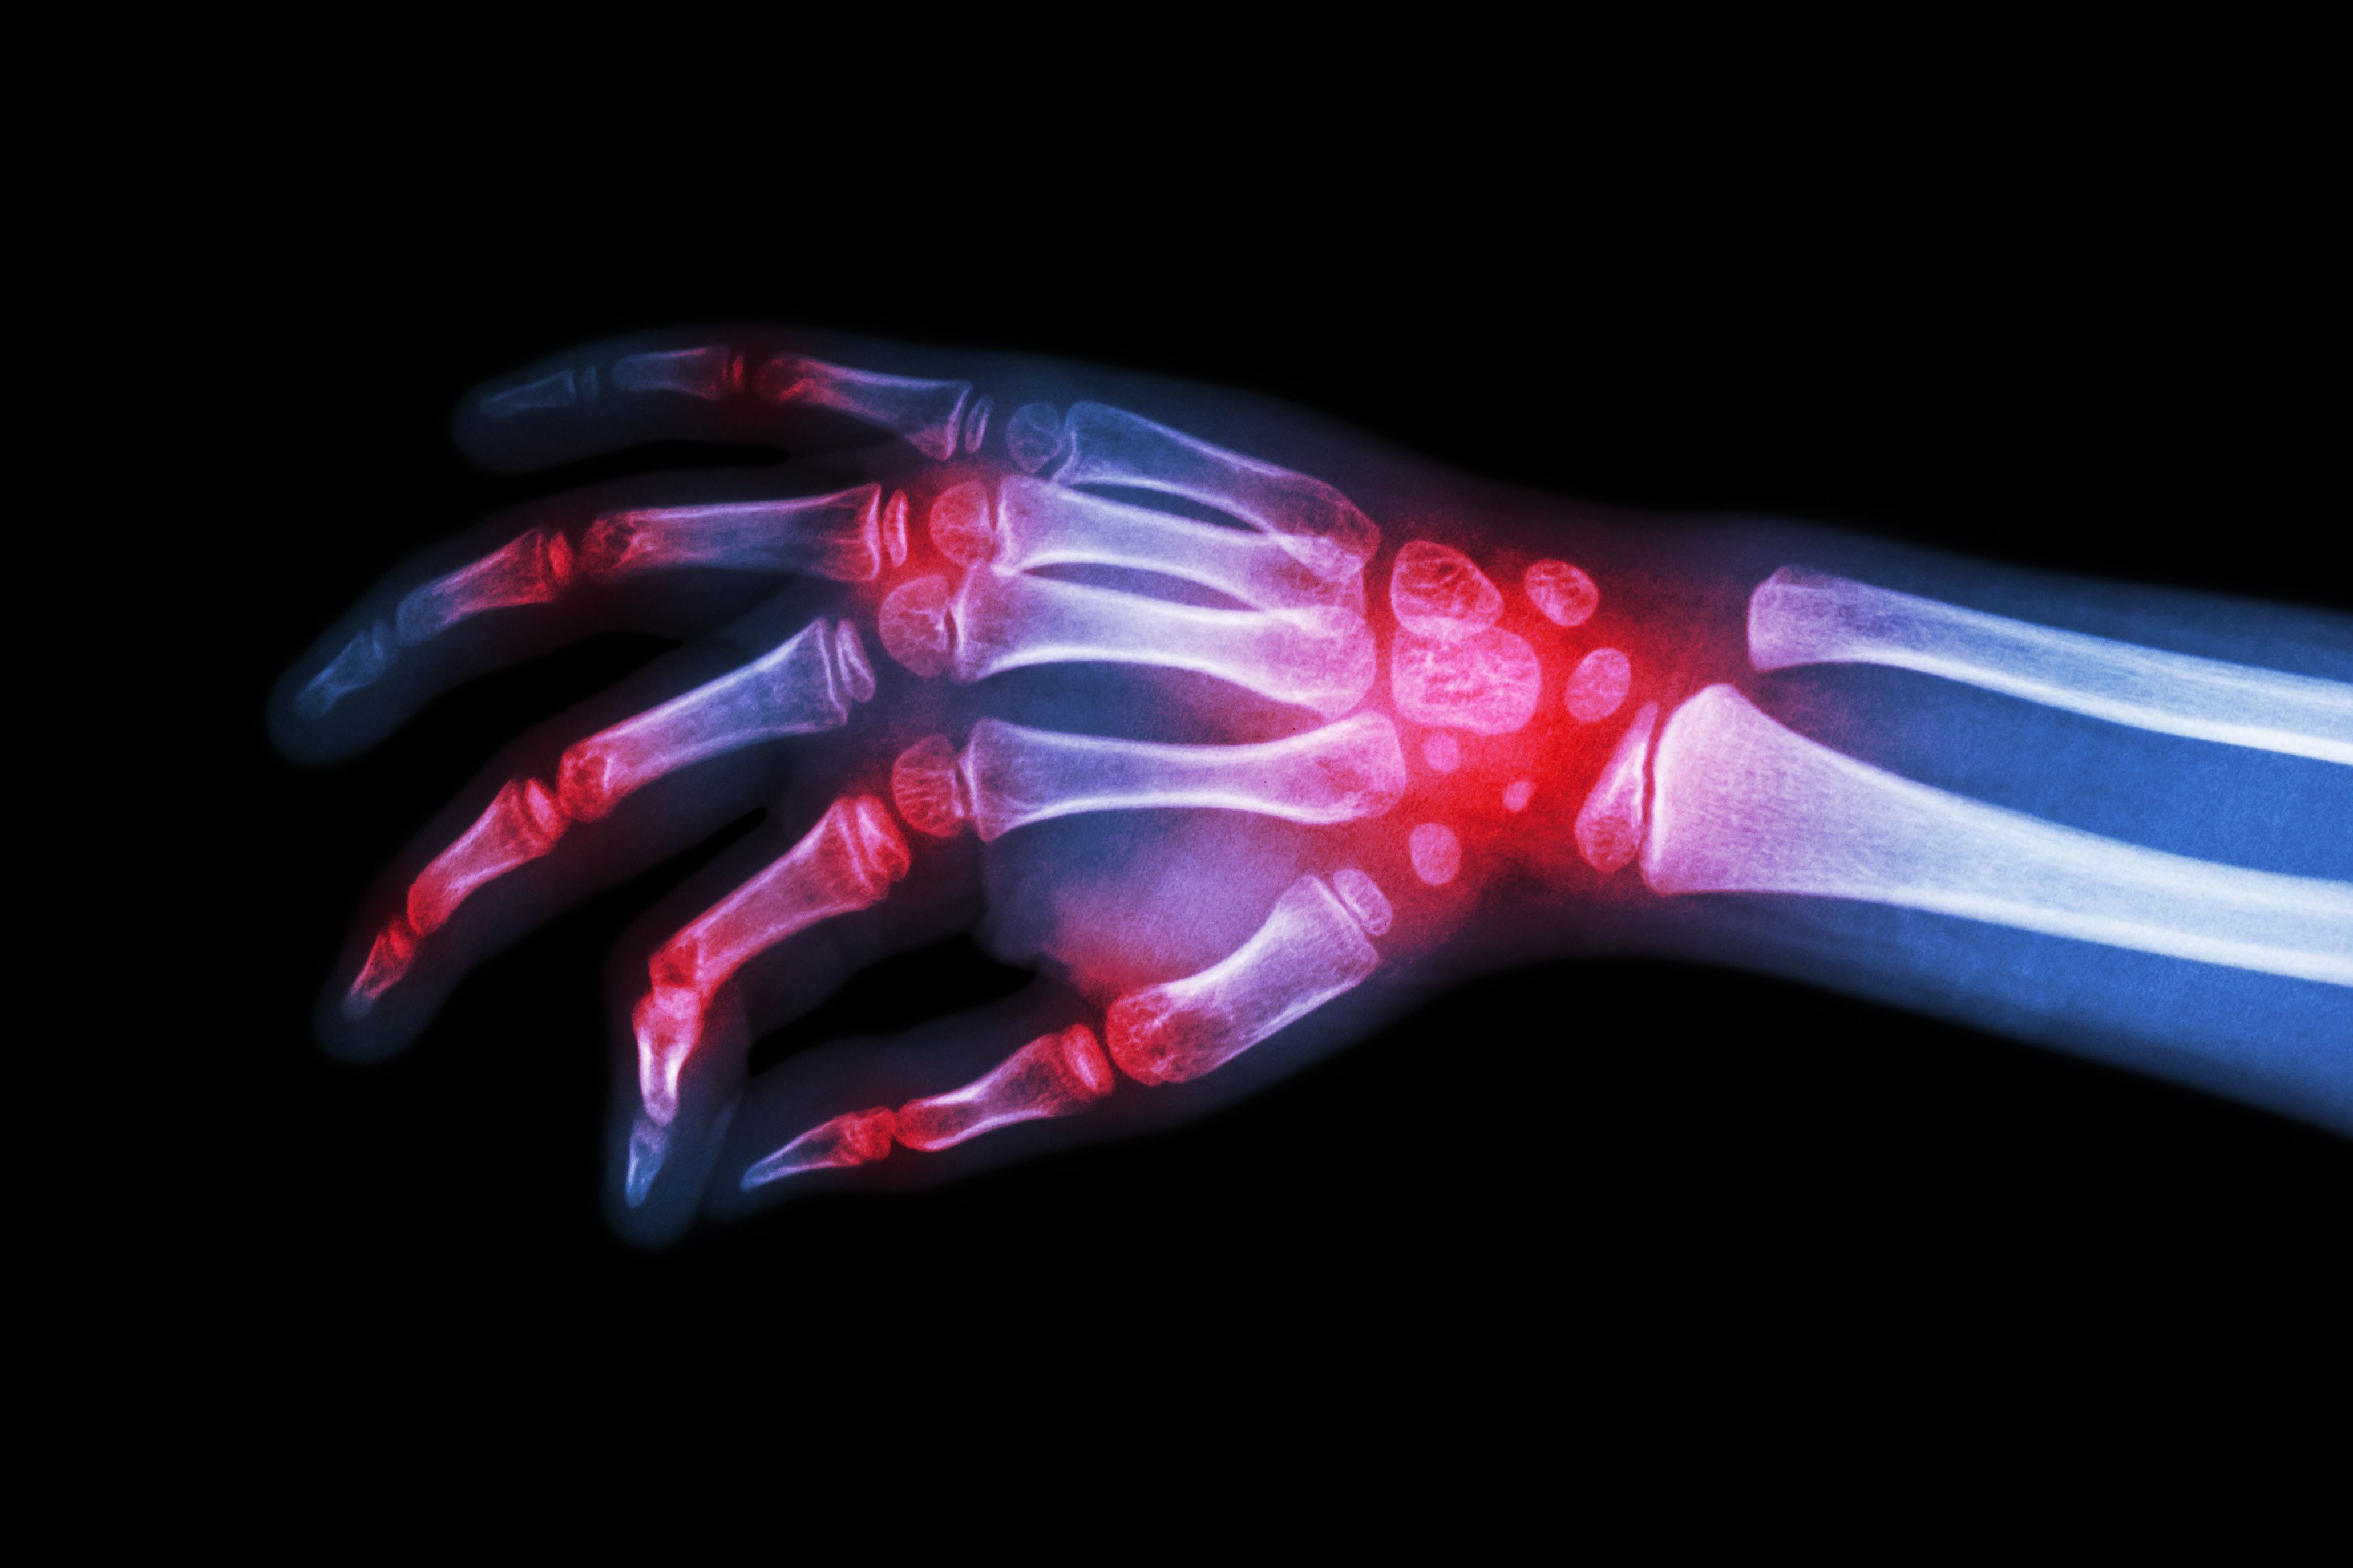

Patients who continued with their rheumatoid arthritis biologic medication tended to spend less on healthcare, had a lower chance of being hospitalized, and had shorter hospital stays.